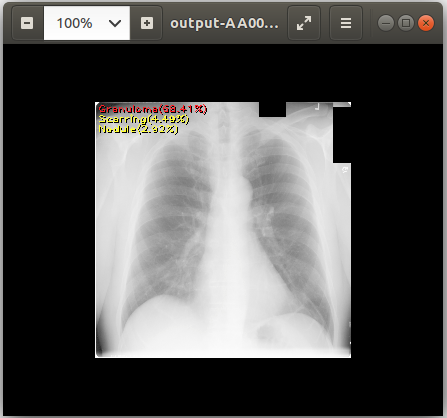

cat output-AA0007572607123433_v2.csv # View text output eog output-AA0007572607123433_v2.png # View image output using `eog` which is an image viewer available in Ubuntu

chest_xray_example_output.png